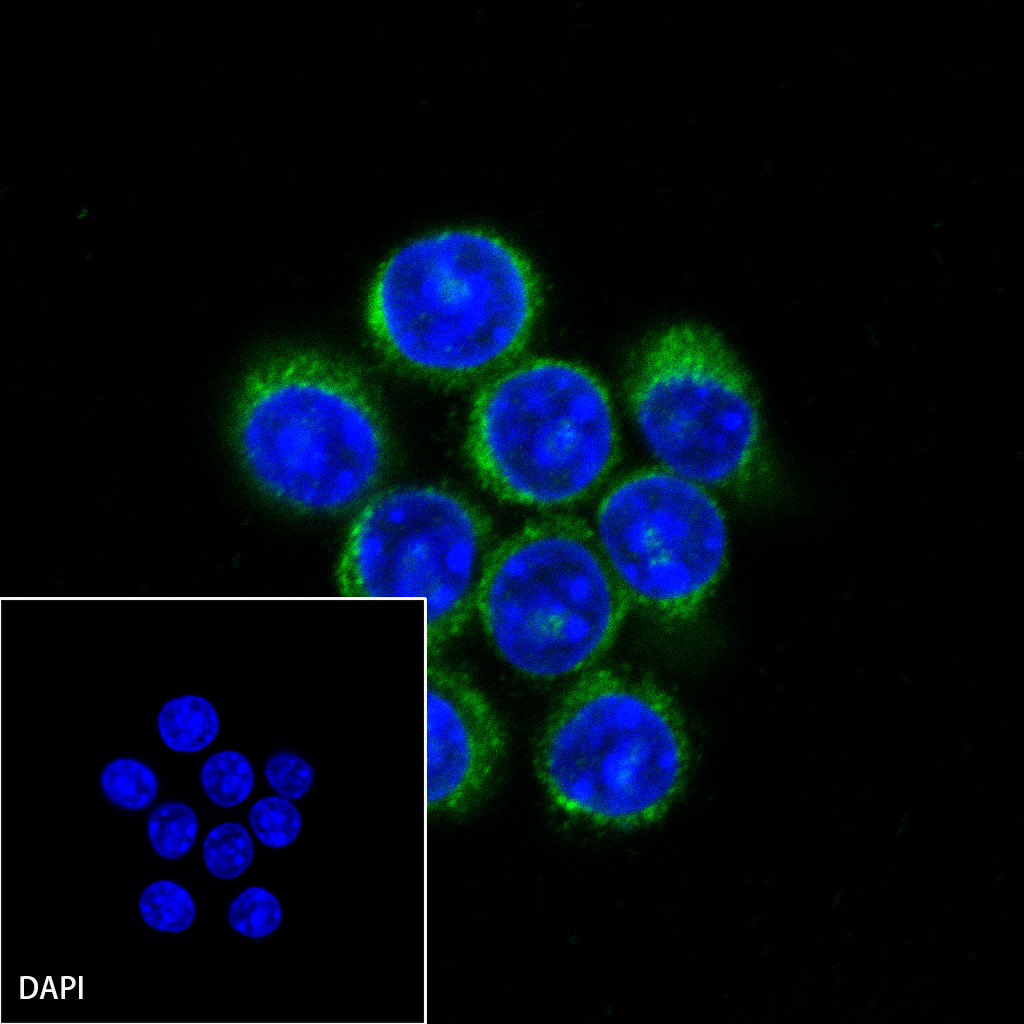

ICC shows positive staining in RAW264.7 cells. Anti-CD68 antibody was used at 1/250 dilution (Green) and incubated overnight at 4°C. Goat polyclonal Antibody to Mouse IgG - H&L (Alexa Fluor® 488) was used as secondary antibody at 1/1000 dilution. The cells were fixed with 100% ice-cold methanol and permeabilized with 0.1% PBS-Triton X-100. Nuclei were counterstained with DAPI (Blue).